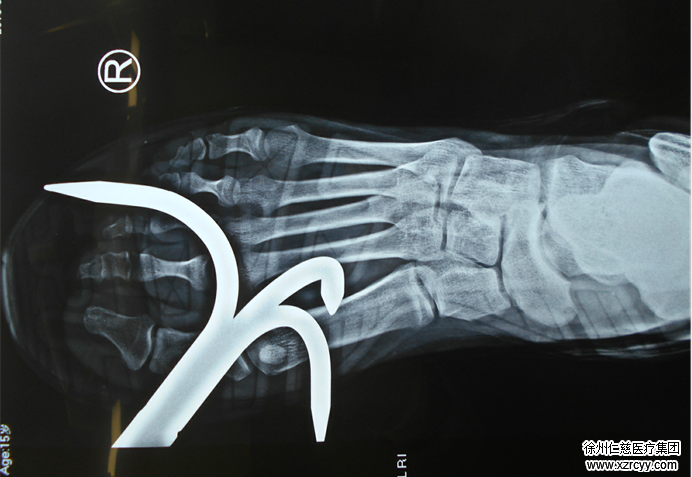

尚卫国医生介绍,因为钩子较大,将鞋子卡住,看不清具体情况,只能用剪刀将鞋子剪碎。后洋洋被紧急送到手术室进行手术。经过四个多小时的手术,钩子被取了出来。